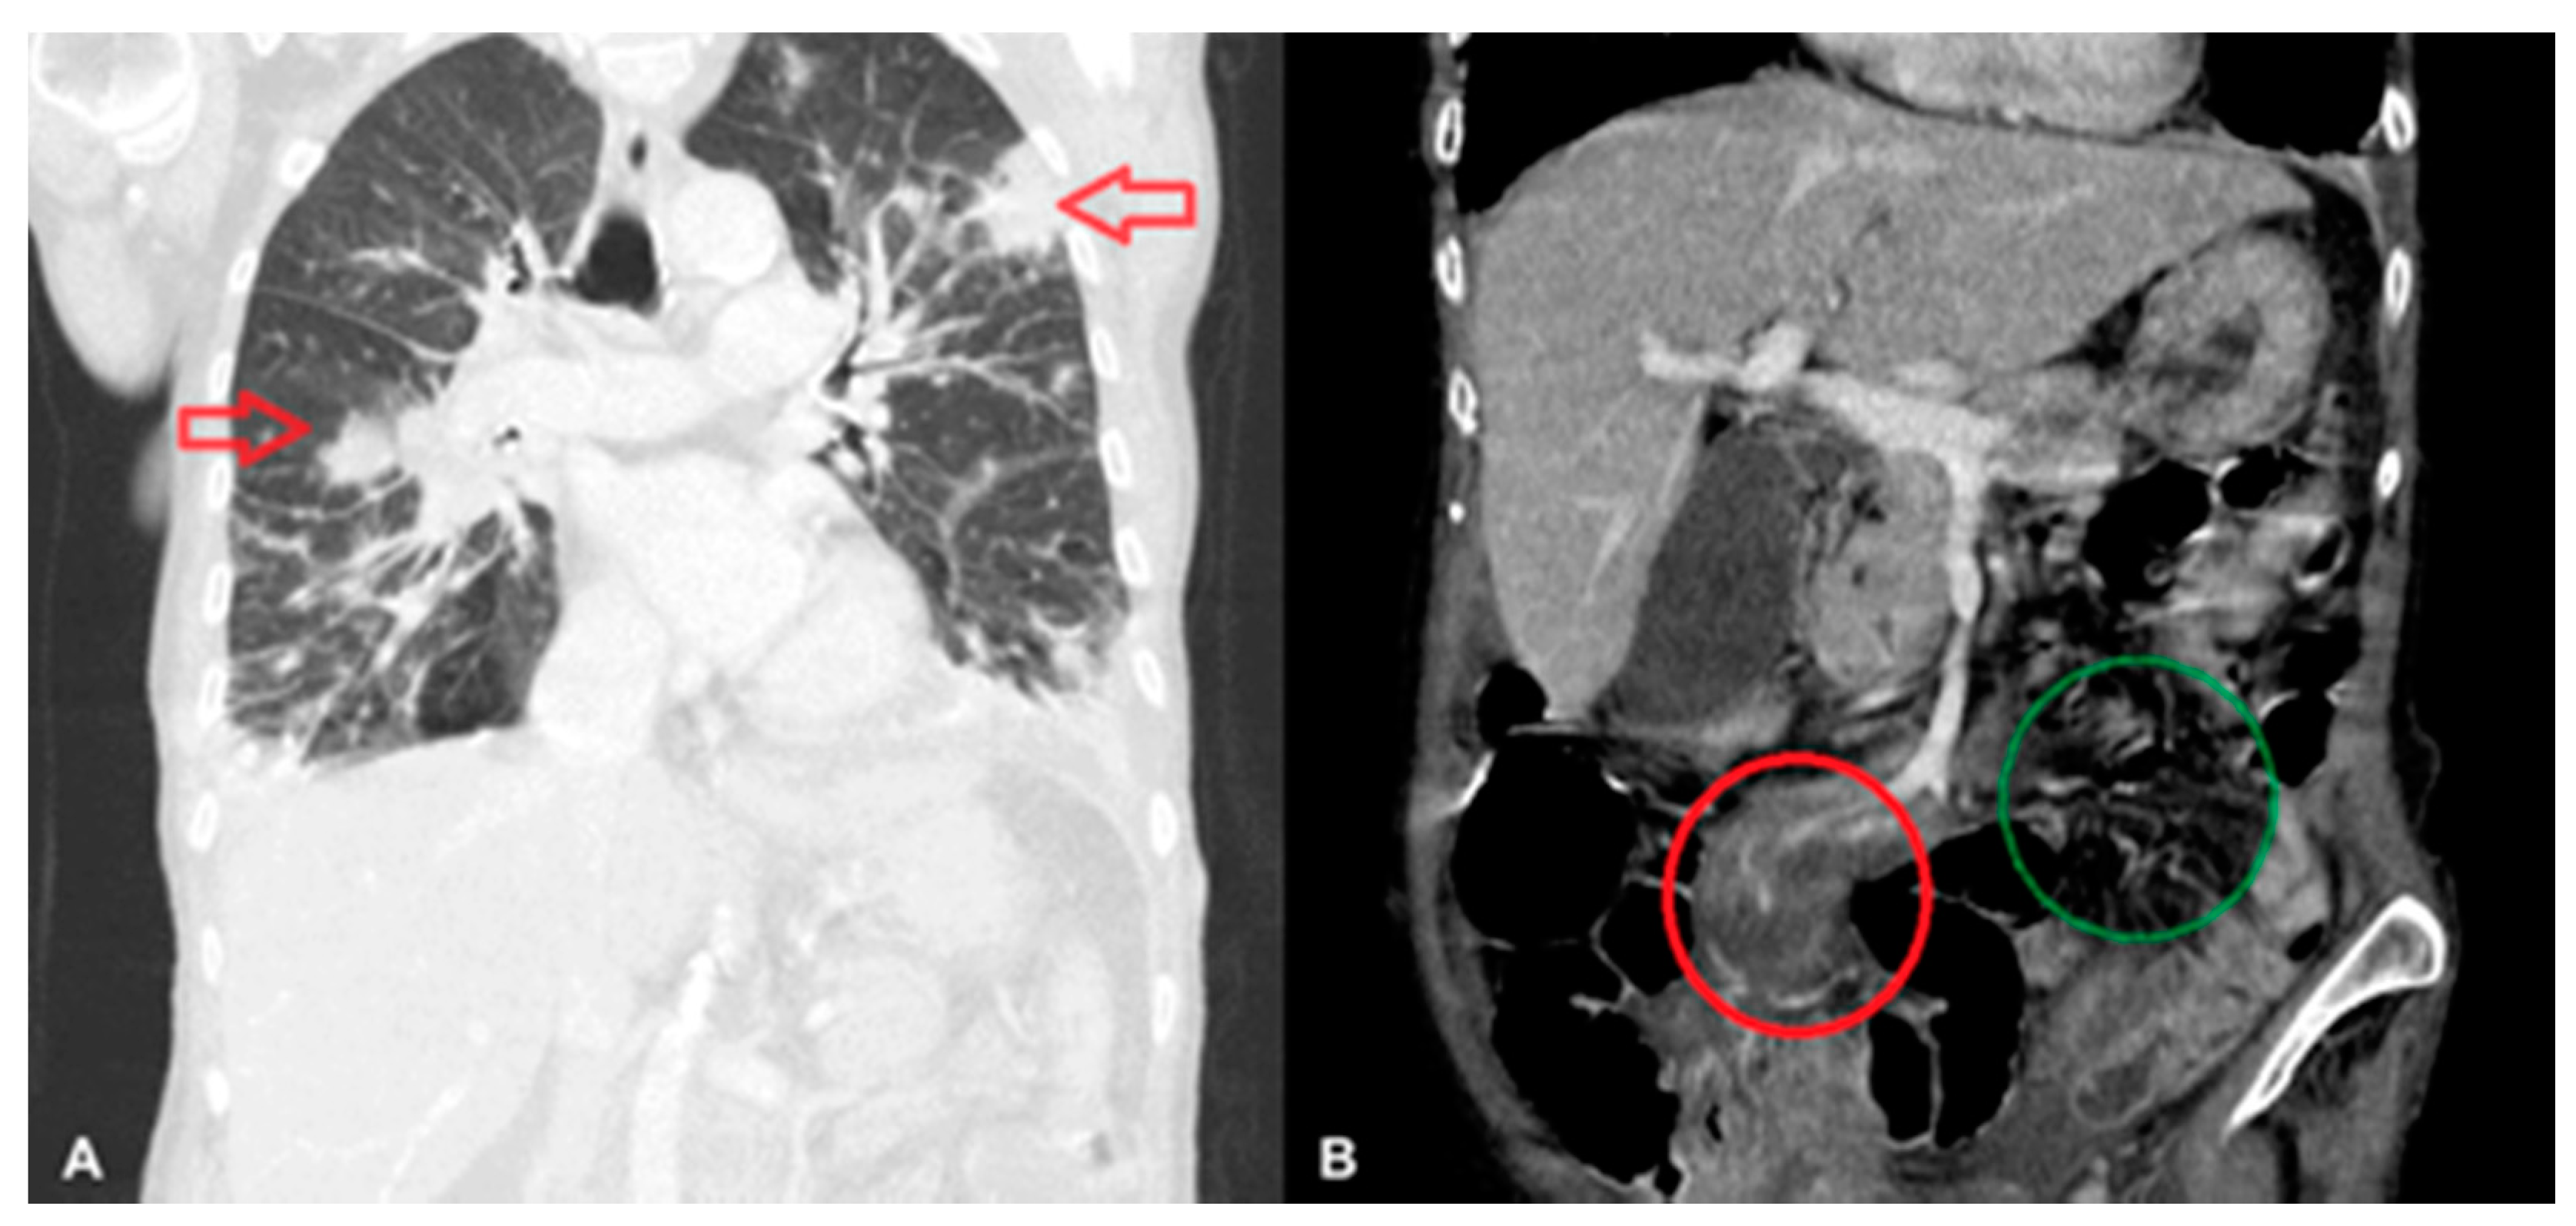

Abdominal, pelvic, and chest computed tomography (CT) scans confirmed a recanalized ureter with leakage of urine into the abdominal wall and patterns characteristic of pneumonia (Figure 1A). The abdominal CT scan also revealed a lymph node 20 × 12 mm to the left of the aorta, a small spleen (56 mm long), an increased density of periaortic fat tissue, and free fluid on the border of the abdominal cavity and pelvis—all described as postoperative, inflammatory, or cardiac-failure-related changes (Figure 1B).

Figure 1. Lymphomatous infiltration of the lungs (indicated by arrows) (A), and of the mesentery of the small intestine (in the red circle); the right mesentery is shown in the green circle (B).